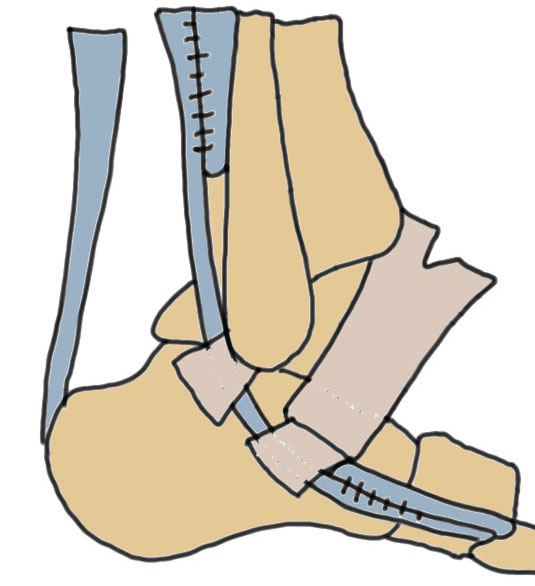

Both tendon tears > 50%

Lateral transfer of FHL / FDL

Vumedi FHL transfer for peroneal tendon rupture video

Harvest donor tendon at Knot of Henry

- pass posteriorly around tibia / fibular

- tenodesis to tendon proximally or to base of 5th metatarsal

Jockel et al Foot Ankle Int 2013

- 8 patients with FHL / FDL transfer for severe P longus and P brevis pathology

- 7/8 good or excellent results

Allograft reconstruction

Mook et al Foot Ankle Int 2013

- 14 patients undergoing allograft reconstruction

- reductions in pain / improvement in function and strength